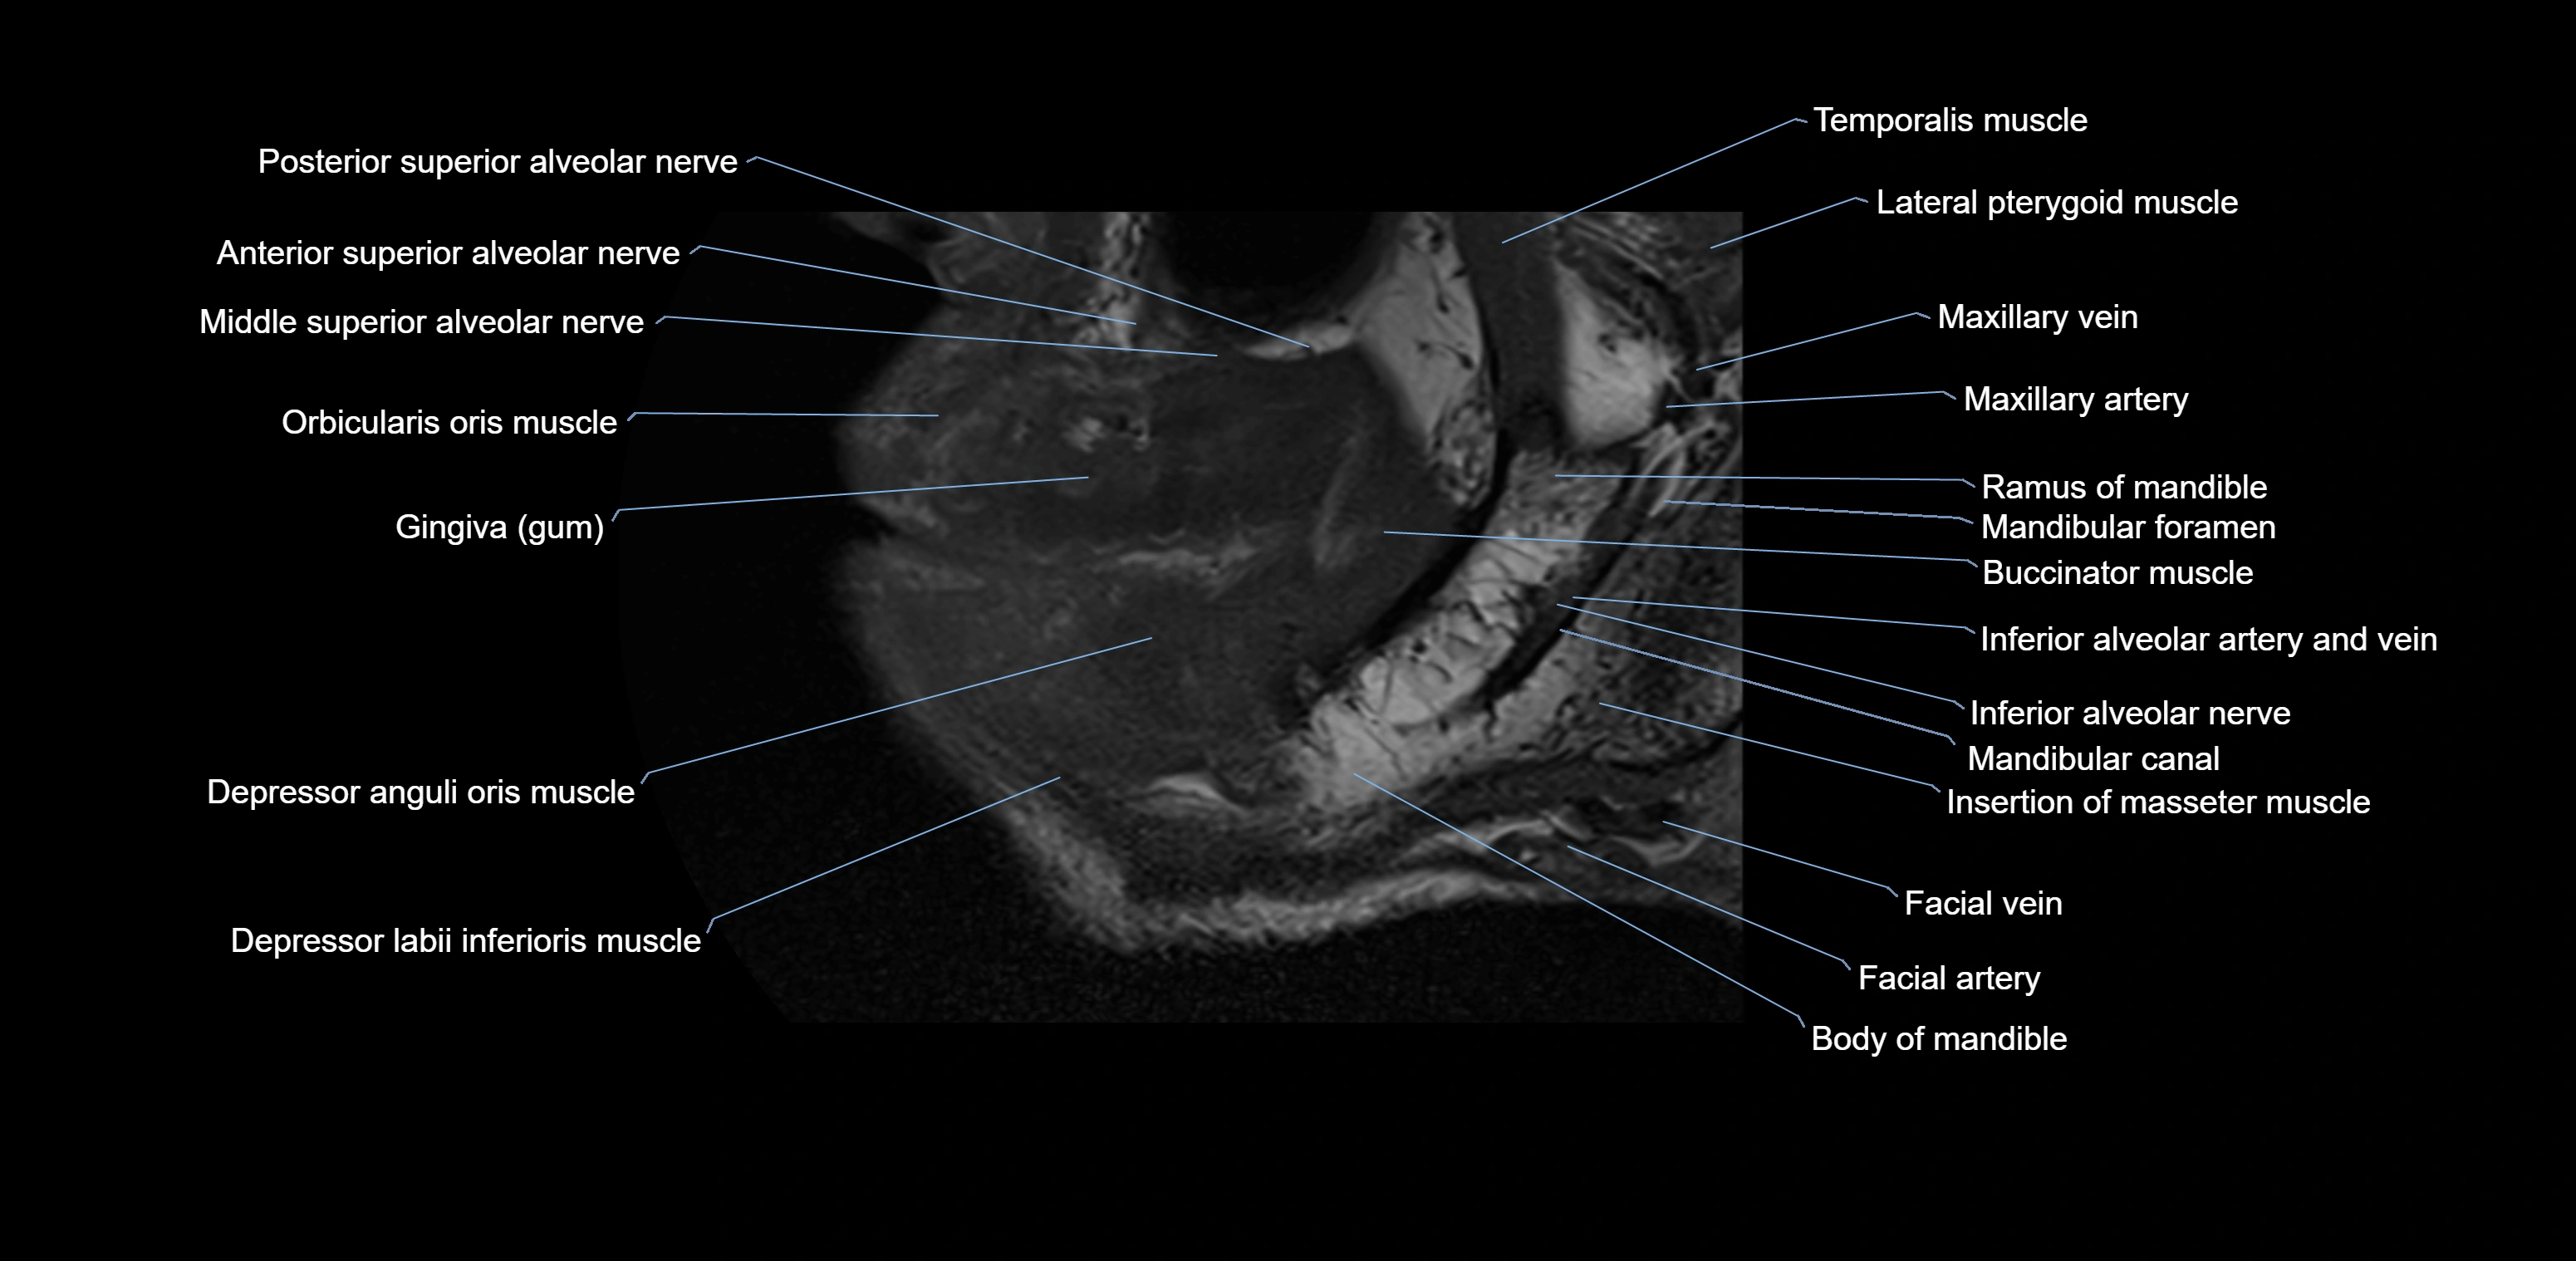

- Anterior superior alveolar nerve

- Body of mandible

- Buccinator muscle

- Depressor anguli oris muscle

- Depressor labii inferioris muscle

- Inferior alveolar nerve

- Mandibular canal

- Mandibular foramen

- Middle superior alveolar nerve

- Posterior superior alveolar nerve

- Ramus of mandible